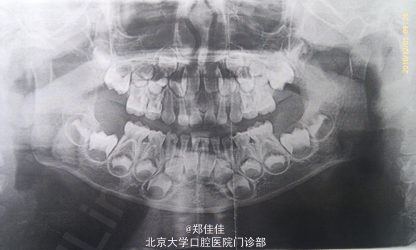

主诉:上前牙外伤2天余

诊断:51,61牙根外吸收+牙震荡 处置:密切观察,必要时拔除